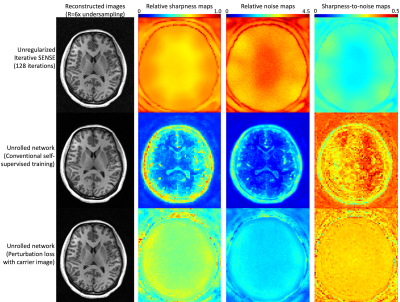

Perturbation loss with carrier image reconstruction: A loss function for optimized point spread functions |

Keywords: Machine Learning/Artificial Intelligence, Image Reconstruction Deep learning (DL) assisted image reconstructions are becoming state-of-the art, producing better image quality and/or enabling higher acceleration rates than achievable with conventional methods. DL networks are used to mitigate noise amplification while retaining important signal characteristics. However, typical loss functions produce object-dependent noise alterations and non-uniform point-spread functions. Here we present a method for training networks that prioritizes maximizing the point spread function to ensure maximal detail retention. |